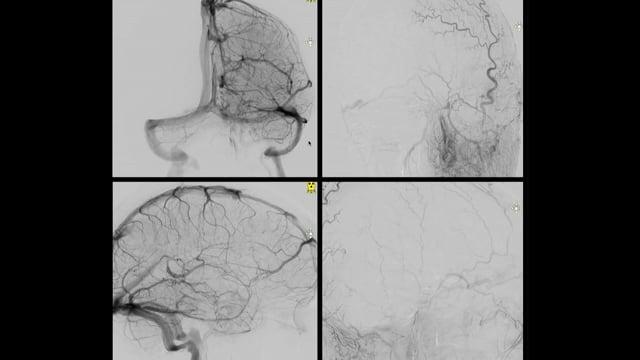

Dive into a curated collection of compelling clinical cases shared by leading experts from LINNC Paris, LINNC Seminars, and LINNC online. Discover a diverse array of complex cases, including aneurysm embolization, AVM/fistula management, stroke interventions, and cSDH treatment. Each case study provides an in-depth exploration of advanced procedures, innovative techniques, and their real-world applications in diagnosing and managing neurovascular conditions.

Snare Wars - May the fix be with you

AneurysmsIntrasacular devices